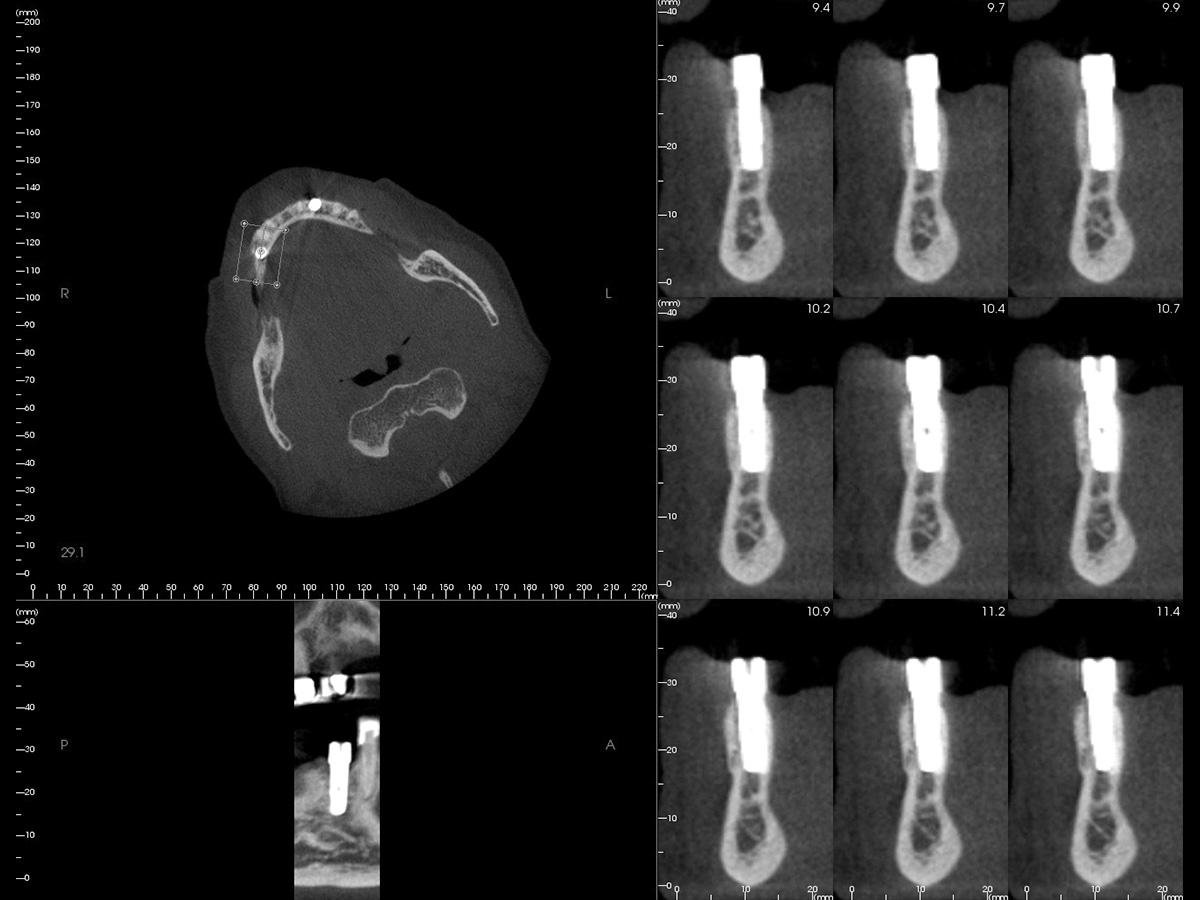

Abbildung 3

3D-Darstellung der geplanten Implantatposition.